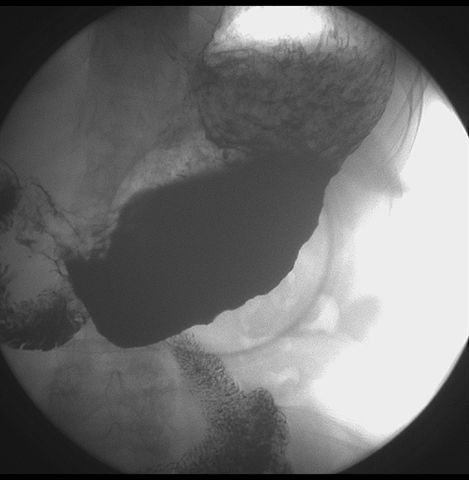

标题: X6872:F,69y,胃部不适。

胃窦至幽门段胃壁僵硬,扩张受限,局部纠集粘破坏,呈杵状。提示溃疡癌变可能性大。

支持考虑胃窦癌可能,胃内滞留液太多,胃窦部僵硬。

瀑布型胃,胃粘膜那是一个乱,窦部充盈不好,第16幅窦部粘膜反倒又很顺,先定个胃炎胃窦炎胃窦癌待排之类,建议进一步作胃镜检查。

胃窦部见钡池影,局部粘膜紊乱,纠集呈杵状改变,胃壁扩张受限,胃窦癌可能性大,建议胃镜检查.

胃窦部管腔扩张度较差,形态略有改变,胃窦粘膜显示欠佳,胃窦部占位可能性大,结合胃镜活检。

北京肿瘤医院胃镜诊断皮革胃。